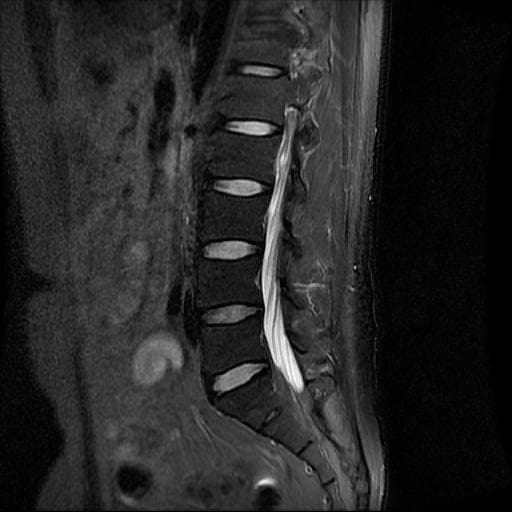

이번에 허리 MRI찍었는데

상태 어떤지 고견 여쭙습니다.

큰 이상이나 문제점은 없어 보이는 것으로 생각되는데요, 허리통증이 지속되는 경우에는 반드시 디스크 질환에 의한것은 아닐 수 있습니다.

우선 사진만으론 정확히 판단 할 수 없기에 전문의에 소견을 들어보시길 추천드립니다.

현재로썬 디스크 상태는 심하지않는것으로 확인이 됩니다.

MRI 영상 커트로 판독을 할 수는 없습니다.

전체 커트를 올리시던가 아시면 판독지를 올려주시면 도움을 드릴 수 있습니다.